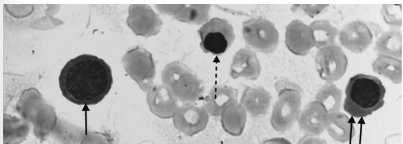

A imagem a seguir remete a um exame de contagem de reticulócitos, no qual foi observada a presença de três diferentes tipos de eritroblastos em fases de maturação diferentes.

Disponível em: https://laces.icb.ufg.br/p/20104-alteracoes-patologicasserie-vermelha-sangue-periferico. Acesso em: 8 out. 2024.

Quais tipos de eritroblastos (indicados pela seta contínua, seta tracejada e as duas setas contínuas, respectivamente) deverão constar no laudo desse exame?